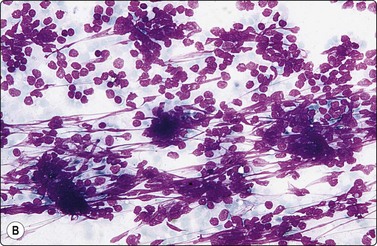

If tissue fragments are not available, immunostaining can be performed on direct smears, or on smears derived from a cell suspension using the cytocentrifuge (Fig. 2.24). Alcohol-fixed smears are usually preferable to air-dried smears. ThinPrep slides of FNAC material have been found highly suitable for immunocytochemical staining.45,46 This technique has the advantage of eliminating background interference by blood and debris (see liquid-based cytology below). The limited number of tests possible when only smears are available can be increased by circling areas 3 mm apart on the same slide with a diamond pencil and wiping the smear between. This allows 2–3 different tests per slide. De-stained previously Pap-stained smears can be used, although poor attachment of the cells to the slide can be a problem.47 Sections of alcohol-fixed and paraffin-embedded cell ‘buttons’ are a good alternative to tissue cores and cell blocks (Fig. 2.25 and see Fig. 2.16).

image image

Fig. 2.24 Immunoperoxidase staining

Smears of non-Hodgkin’s lymphoma. (A) Direct smear; interpretation difficult due to background staining caused by fragmentation of cytoplasm; (B) Cytocentrifuge preparation; positive staining distinctly related to individual cells (HP).

image

Fig. 2.25 Immunoperoxidase staining

‘Cell button’ of FNB sample of non-Hodgkin’s B-cell lymphoma; (A) Tissue section, H&E; (B) Positive staining with a pan-B marker; (C) negative staining with a pan-T marker (IP).